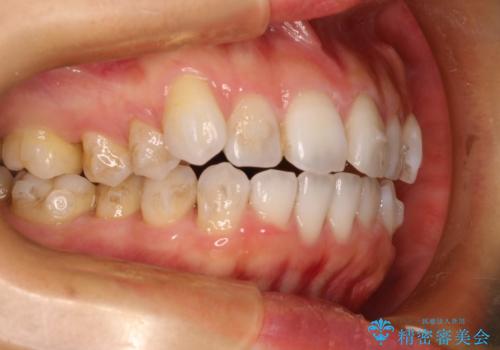

抜歯せずに八重歯のマウスピース矯正

- 非抜歯・遠心移動+IPR+拡大 によるマウスピース矯正を計画した。

八重歯がシビアな場合、抜歯をしないと治せないケースもありますが、奥歯の位置関係を修正したり、歯のサイズダウンを行うことで、抜歯をせずに改善できる場合もたくさんあります。